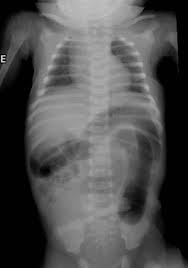

The abdominal radiograph

1.Typicall  a low bowel obstruction, commonly with colonic dilatation out of proportion to the small bowel.

2.The absence of rectal gas is characteristic

3.About 5% of infants have a pneumoperitoneum

4.Intraluminal small bowel calcifications .